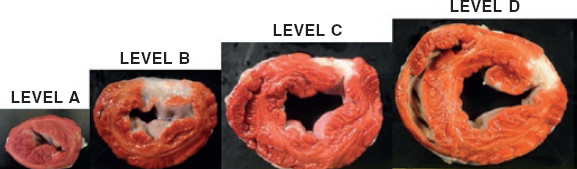

A complete, organized, and systematic necropsy of each animal corpse was conducted to identify and diagnose any possible conditions associated with the procedure. The samples obtained were fixed in formaldehyde at 10% for histopathological study. In the macroscopic study of the heart, its weight was recorded and its cavities, walls, papillary muscles, mitral chordae tendinae, annulus, and valve leaflets analyzed. All the possible anomalies seen in these structures were documented photographically. Afterwards, the leaflets were extracted from their insertion location and up to their free borders including their chordae tendinae and they were fixed in formaldehyde at 10% and included in paraffin for histopathological study. Three µm thick serial sections were stained with the usual hematoxylin and eosin technique; the Van Gieson elastin stain protocol was used to study elastic and collagen fibers; the Masson trichrome stain protocol was used to differentiate muscular from collagen fibers; finally, the alcian-blue PAS staining protocol was used for the detection of mucopolysaccharides. The histopathological changes identified were semi-quantitatively assessed by establishing the different degrees of damage.

After collecting the leaflets to characterize the infarction, another 4 cross-sectional cuts were performed from the vertex of the heart towards its base. They were weighted and stained with triphenyltetrazolium chloride histochemical staining to enhance the viable area (red color) of the necrotic region (white color). For that purposes, the levels established were submerged in a solution of triphenyltetrazolium chloride (Sigma-Aldrich) at 1% in a phosphate buffered saline solution (pH 7.4) for 5 to 10 minutes at 37 °C, and then they were submerged in formaldehyde at 10%. The sections were photographed, and the areas measured using the Image J system. Samples of the infarction region, limit, and non-infarcted region were collected from every level, submerged in paraffin, and stained using the hematoxylin and eosin technique and the Masson trichrome stain protocol to characterize ischemic damage.

Animal #2

The macroscopic evaluation revealed the presence of a transparietal infarction region in the posterior side damaging the medium and basal segments (figure 3) and papillary muscle (figure 4). The spread of this lesion into the different levels is shown on table 2 of the supplementary data.

Figure 3. Animal #2. Presence of transparietal infarction areas from medium (B) to basal level (D). Triphenyltetrazolium chloride stain.